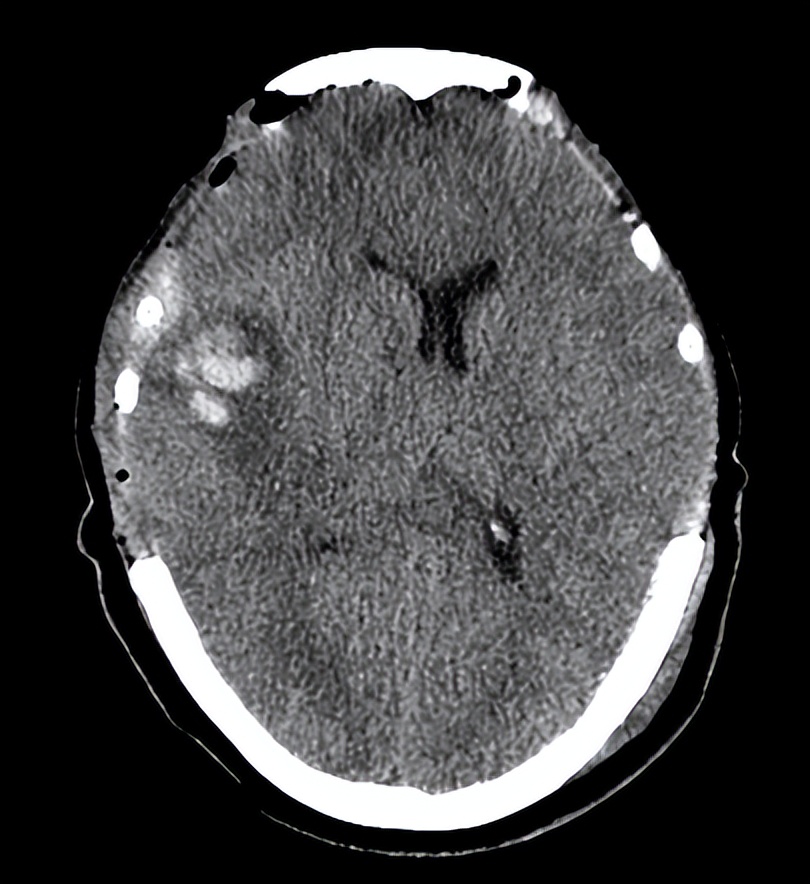

06-20复查头CT

神志昏睡状,GCS评分8T分(E4MTV4)双侧瞳孔3.0mm,对光反射灵敏。骨窗张力不高。双肺呼吸音清,下肺闻及散在湿罗音。四肢肌力检查不配合,左侧肢体未见肌肉收缩,双侧巴氏征阳性。此时我不在现场,科主任给我发了6月20日的头颅CT,和患者当时的病情描述,并拍了患者的照片发送给我。我考虑患者受到如此严重的颅脑创伤,身体元气大伤,如果不及时补益,即使生命保住,很可能留下严重后遗症。